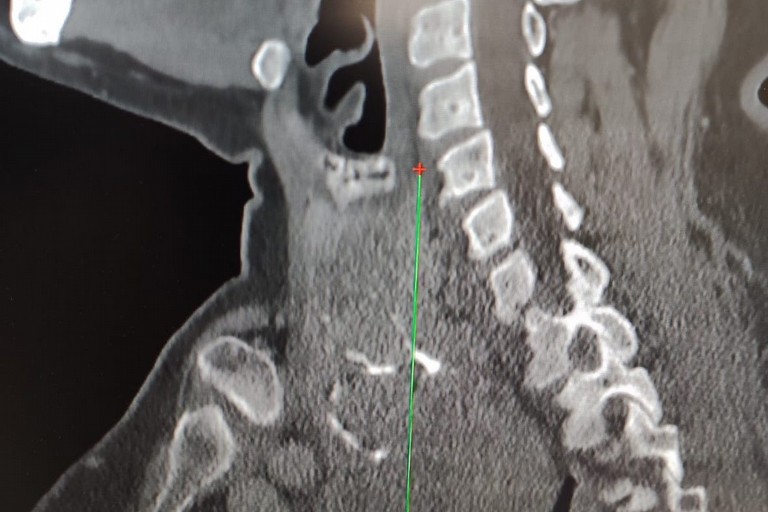

"Gli accertamenti radiologici – spiega il dottor Luigi Madami, otorinolaringoiatra che ha eseguito l'intervento nell'Unità operativa diretta dal prof. Nicola Quaranta – hanno mostrato che la tiroide era ingrandita, con un'estensione di circa sette centimetri, si estendeva nel mediastino (la parte alta del torace) e spingeva la trachea verso sinistra, pur lasciandola libera nel passaggio dell'aria. Erano presenti anche piccoli noduli e calcificazioni. L'intervento di rimozione della tiroide (tiroidectomia) è stato eseguito con un approccio sternotomico, cioè aprendo parzialmente lo sterno grazie alla collaborazione multidisciplinare con i cardiochirurghi".